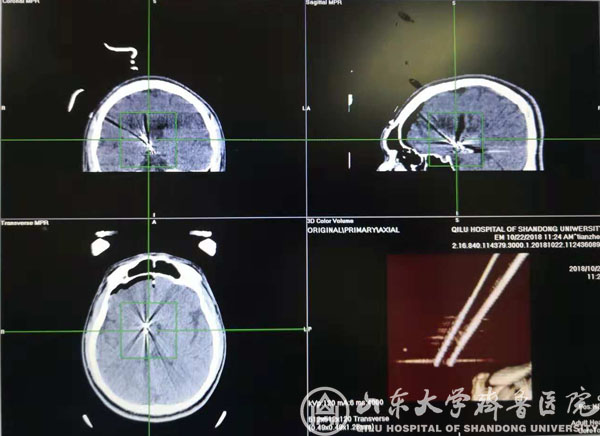

术中CT验证靶点

该患者男,20岁,发作性头痛、痴笑、左眼向上凝视病史11年,口服丙戊酸钠、拉莫三嗪、鲁米那等多种抗癫痫药物效果欠佳,每日痫性发作仍3~6次,颅脑MRI提示右侧丘脑前下部占位性病变,考虑下丘脑错构瘤。患者收入我院功能神经外科病房后,赵秀鹤副主任带领神经内外科团队共同对患者进行了充分的术前评估,对手术方案进行了深入的讨论,考虑到病变位置重要且深在,开放性开颅手术风险高,术后并发症发生率高,最后决定采用立体定向脑电图引导下射频热凝术的治疗方案。10月21日,徐淑军主任、徐硕主治医师为患者制定了SEEG方案,并在手术机器人引导下成功将颅内电极埋藏在预设手术靶点。经术中CT、多模态影像融合技术以及立体定向脑电监测等多种手段验证靶点后,对致痫灶实施精准射频热凝。术后患者癫痫发作频率较术前减少,未见明显不良反应,已顺利出院,长期疗效正在随访观察中。

作为新兴的癫痫病灶诊断与定位技术,SEEG通过埋藏颅内电极的方式精准捕捉致痫灶起源并明确癫痫传播网络,为难治性癫痫的外科治疗提供依据,必要时还可通过电极热凝对位置较深、范围较小或位于功能区的病变进行毁损,发挥治疗作用。由于对定位精准度要求极高(以毫米计算),传统SEEG电极植入主要依靠立体定向框架系统,但手术操作繁琐,耗时较长,且需要在患者局部麻醉下安装立体定向头架,增加患者心理压力。神经外科手术机器人系统通过无框架定位技术与机械臂辅助,在保证手术精度的同时,简化SEEG手术过程,缩短手术时间,改善患者体验。本次手术是手术机器人系统在我院神经外科首次亮相。除SEEG外,未来机器人还有望应用于颅内病变活检、血肿穿刺引流、术中导航甚至脑深部电刺激器植入等神经外科手术。